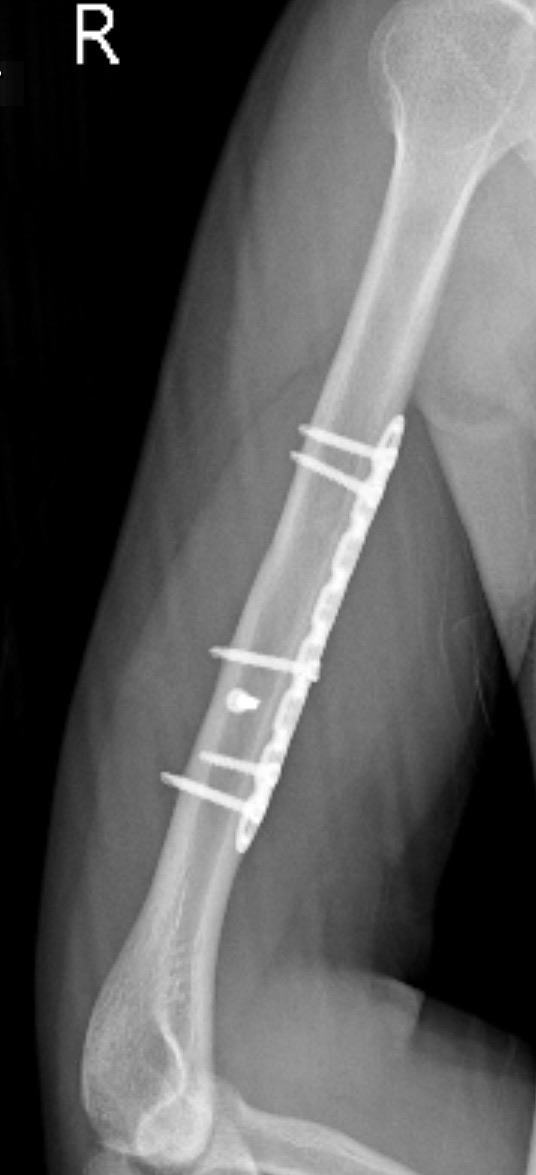

Bác sĩ ơi cho em hỏi đây là ảnh phim sau 1 năm gãy xương cánh tay của em, qua ảnh thì xương của em đã liền được tốt chưa ạ và có thể chơi thể thao chưa ạ

Hình ảnh liền xương tốt rồi em. Tuy nhiên chưa nên chơi thể thao sớm. Em có thể tham khảo ý kiến bác sĩ phẫu thuật